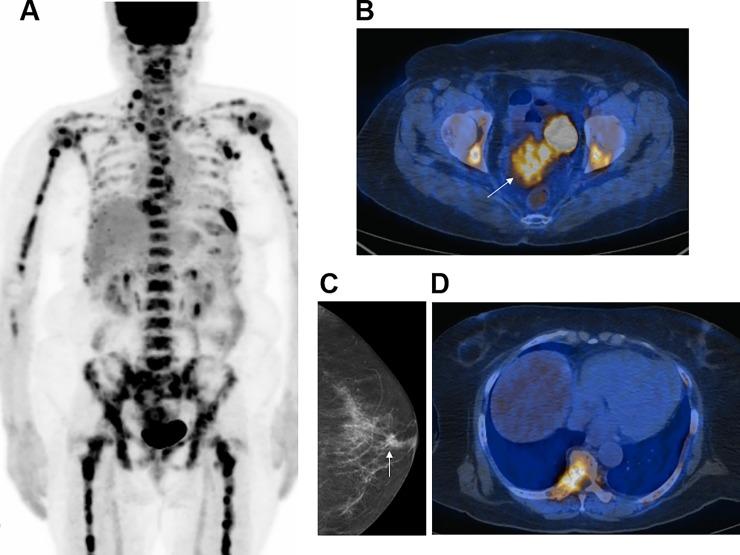

When subjects without a known malignancy present with suspicious skeletal lesions, differential diagnosis and primary cancer identification is important. Here, we investigated the role of FDG PET/CT in this clinical situation.

We enrolled 103 patients with no known malignancies who were referred for FDG PET/CT because of bone lesions that were suspicious for cancer metastasis. Each extra-skeletal FDG lesion was categorized as consistent with primary cancer or with metastasis based on the distribution and pattern of all abnormal lesions in the individual.

Final diagnosis revealed that bone lesions represented cancer metastasis in 75 patients (72.8%). In the remaining 28 patients (27.2%), they were from other causes including multiple myeloma or lymphoma, malignant primary bone tumor, and benign bone disease. PET/CT indicated a primary cancer in 70 patients (68.0%). This was the correct primary site in 46 cases and the incorrect site in 13 cases (including 6 cases with cancer of unknown primary, CUP). In the remaining 11 cases, the bone lesions were due to other causes. PET/CT did not indicate a primary cancer in 33 patients (32.0%). Of these cases, 17 did not have a primary cancer, 8 had CUP, and 8 had primary cancers that were missed. Thus, PET/CT had a sensitivity of 61.3% and specificity of 60.7% for primary cancer identification in the entire population. Excluding patients with CUP, PET/CT sensitivity was 75.4%. PET/CT also provided information useful for recognizing multiple myeloma and benign bone disease as the cause of the skeletal lesions.

In patients without known malignancies with suspected skeletal cancer metastasis, FDG PET/CT can help identify the primary cancer and provide useful information for differential diagnosis.

当没有已知恶性肿瘤的患者出现可疑的骨骼病变时,鉴别诊断和确定原发性癌症非常重要。在这里,我们研究了 FDG PET/CT 在这种临床情况下的作用。

我们招募了 103 名没有已知恶性肿瘤的患者,由于骨骼病变疑似癌症转移,他们被转介进行 FDG PET/CT。根据个体中所有异常病变的分布和模式,将每个骨骼外 FDG 病变归类为与原发性癌症一致或与转移一致。

最终诊断显示,75 名患者(72.8%)的骨骼病变代表癌症转移。在其余 28 名患者(27.2%)中,他们患有其他疾病,包括多发性骨髓瘤或淋巴瘤、恶性原发性骨肿瘤和良性骨疾病。PET/CT 在 70 名患者(68.0%)中提示原发性癌症。在 46 例中,这是正确的原发性部位,在 13 例中是错误的部位(包括 6 例癌症未知原发部位,CUP)。在其余 11 例中,骨骼病变是由其他原因引起的。在 33 名患者(32.0%)中,PET/CT 未提示原发性癌症。在这些病例中,17 例没有原发性癌症,8 例患有 CUP,8 例原发性癌症被遗漏。因此,PET/CT 对整个人群原发性癌症的识别具有 61.3%的敏感性和 60.7%的特异性。排除患有 CUP 的患者后,PET/CT 的敏感性为 75.4%。PET/CT 还提供了有助于识别多发性骨髓瘤和良性骨疾病作为骨骼病变原因的有用信息。

在没有已知恶性肿瘤且疑似骨骼癌症转移的患者中,FDG PET/CT 可以帮助识别原发性癌症,并为鉴别诊断提供有用信息。